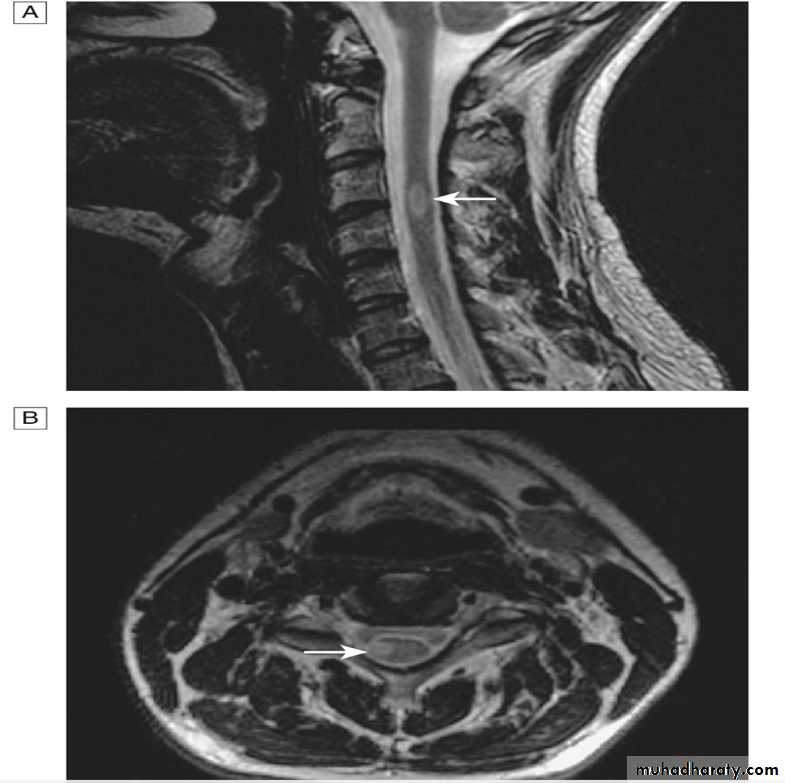

myelitis can be severe and transverse (rare in MS) and is typically longitudinally extensive, involving three or more contiguous vertebral segments

A T2-weighted MRI image of her spinal cord shows a lesion extending from T1 to T5 and affecting the central cord. The lesion shows patchy enhancement with gadolinium.

There is increased T2 signal in the area postrema and around the third ventricle.

TRANSVERSE MYELITIS

The term ‘‘transverse myelitis’’ describes acollection of acute and subacute infectious and noninfectious inflammatory spinal cord syndromes

Transverse myelitis is classified clinically based on whether it is complete or incomplete.

A ‘‘complete’’ cord lesion, which manifests as a relatively symmetric moderate or severe loss of motor and sensory modalities caudal to the level of the lesion, suggests (infectious, or idiopathic transverse myelitis or NMO).

In contrast, a ‘‘partial’’ myelitis syndrome (ie, incomplete or patchy involvement of at least one spinal segment with mild to moderate weakness and asymmetric or dissociated sensory symptoms) is more likely to herald MS.

Neuroimaging characteristics are critical for diagnosis. Identification of an intramedullary cord lesion, especially postgadolinium enhancement, is very helpful in a diagnosis of myelitis